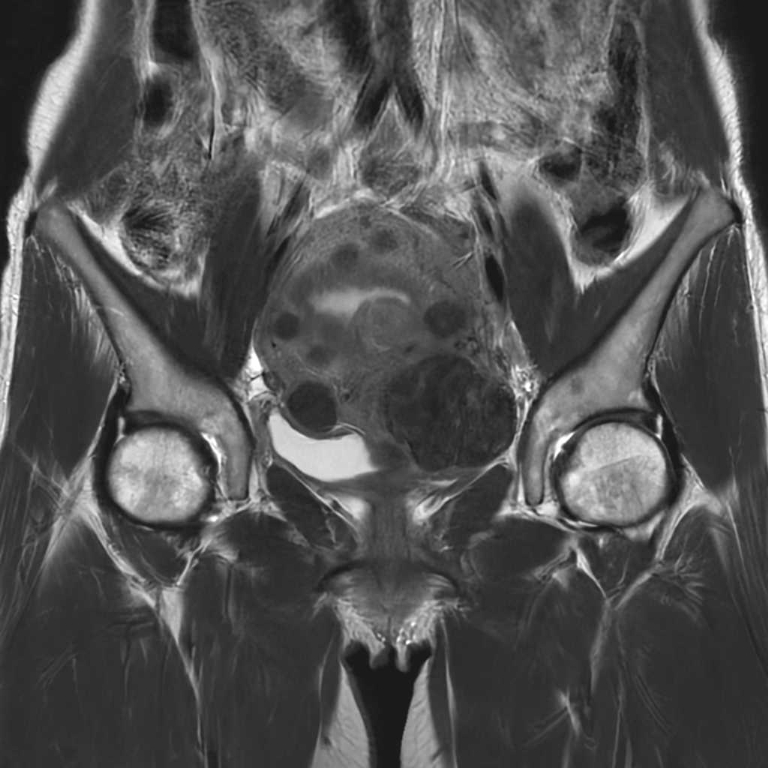

MRI検査

内科領域

男性器領域

前立腺

前立腺肥大